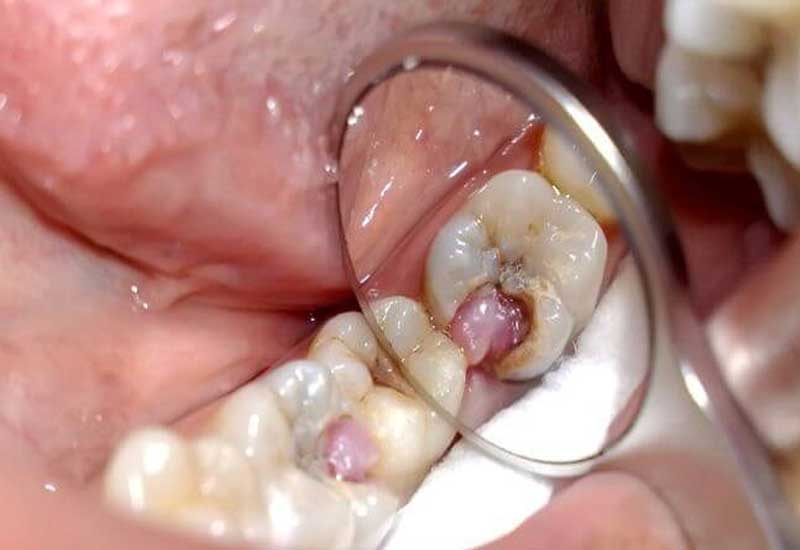

- Nướu bị sưng to, cảm giác đau và mềm khi bóp, dễ chảy máu và đôi khi có mủ chảy ra khi bóp.

- Xuất hiện khối mủ ở vùng chân răng, khi khối mủ vỡ ra có thể giảm đau hơn.

Trên đây là những dấu hiệu mà bạn có thể gặp khi mắc bệnh viêm tủy răng có mủ. Tuy nhiên, trong giai đoạn ban đầu, triệu chứng thường nhẹ nhàng, nên người bệnh thường không chú ý cho đến khi bệnh ảnh hưởng nghiêm trọng đến chất lượng cuộc sống. Do đó, người bệnh cần phải chuẩn bị tinh thần sẵn sàng và không chủ quan, nên tham khảo ý kiến của bác sĩ chuyên khoa răng miệng để nhận được điều trị kịp thời và ngăn ngừa những biến chứng nghiêm trọng.